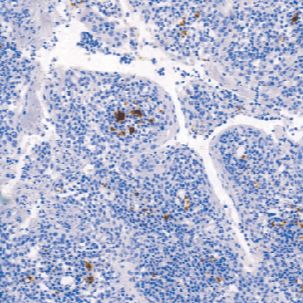

CD61抗原也称为GPllla,是分子量为105kD的糖蛋白,存在于血小板、单核细胞、内皮细胞、平滑肌细胞、B细胞、巨噬细胞、肥大细胞和成纤维细胞中。CD61抗原在血小板聚集中发挥作用,并且还是纤维蛋白原、纤维连接蛋白、vonWillebrand因子和玻连蛋白的受体。据报道,在格兰茨曼(Glanzmann) 血小板无力症的患者中极少或者不表达CD61抗原。大多数巨核细胞白血病的病例表达CD61抗原。

- 阳性部位:胞膜,胞质

- 适用组织:石蜡切片

- 预处理:热修复

文献和实验CD61 分子 CD61 常用单克隆抗体或代号: Y2/51,CLB- thromb/1;(VNR- b 链,integrin b 3) 主要表达细胞: Pt,Meg [Pt] 分子质量(kDa)和结构: gp105,血小板GPⅢa,与CD51组成VNR,与CD41组成a Ⅱbb 3 功 能: 血小板凝集和活化 CD61 Aka platelet glycoprotein IIb